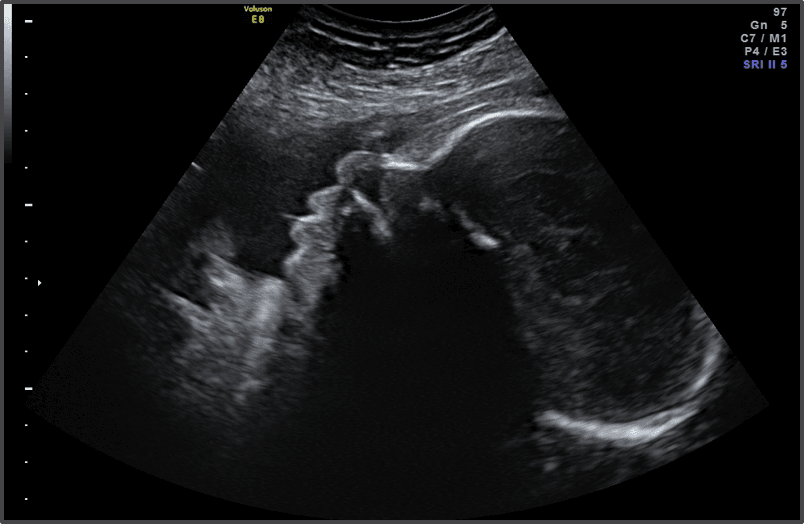

Ултразвук

(35 гестационна седмица)

Слухът на бебето е напълно развит, а вашият 35 седмичен плод реагира най-силно на високо-честотни шумове. Ако сте бременна с момче през 35 гестационна седмица, по време на ултразвука ще видите, че тестисите му вероятно са спаднали напълно и са на правилното си място.

Черепът на бебето e мек – Нещо друго, което се развива с умопомрачителни темпове през 35 гестационна седмица: мозъчната дейност на вашето бебе. За щастие частта, която обгражда този удивителен мозък – черепът – остава мека. И с добра причина: Мекият череп ще позволи на бебето ви да излезе по-лесно през родовия канал.